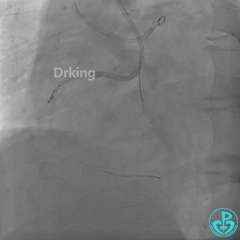

右冠造影:

导丝怎么扩收藏:器械难以通过的CTO病变之技术图谱_https://www.jmylbn.com_新闻资讯_第6张

导丝怎么扩收藏:器械难以通过的CTO病变之技术图谱_https://www.jmylbn.com_新闻资讯_第7张

导丝怎么扩收藏:器械难以通过的CTO病变之技术图谱_https://www.jmylbn.com_新闻资讯_第8张